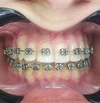

اعوجاج الأسنان